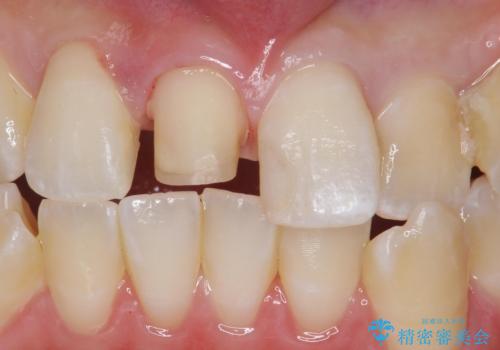

前歯の色が気になる。オールセラミッククラウンでのやり替え

- 前歯のかぶせ物の色が気になるとのことで来院された患者様です。

セラミッククラウンで作り変えていきます。

- 右上1: 仮歯/11,000円、ジルコニアクラウン(スタンダード)/121,000円 合計132,000円(税込)費用は治療当時の料金となります